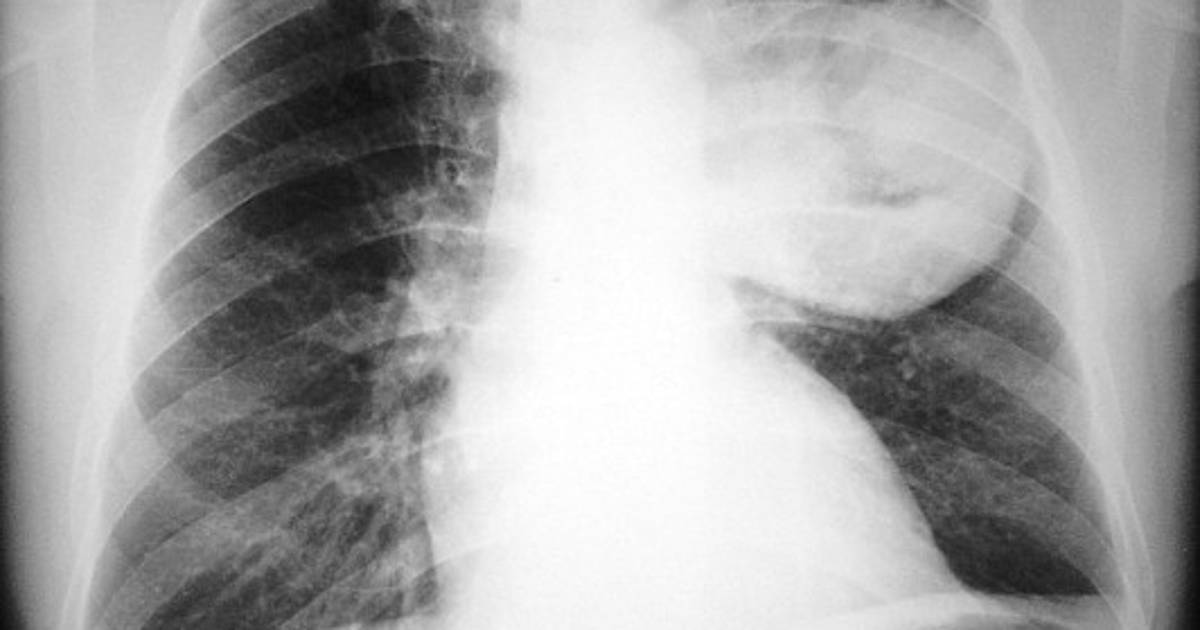

Lo que podría aumentar riesgo de cáncer de pulmón

Las personas que fuman o tienen cáncer de pulmón deberían pensar dos veces antes de tomar suplementos vitamínicos, según un estudio divulgado el miércoles que mostró que ciertos antioxidantes pueden impulsar el crecimiento de tumores malignos.

Los suplementos de vitaminas antioxidantes aceleran el desarrollo de las lesiones precancerosas y el cáncer de pulmón en etapa precoz, indicó este estudio sueco publicado en la revista médica estadounidense Science Translational Medicine, que aclara por primera vez este mecanismo.